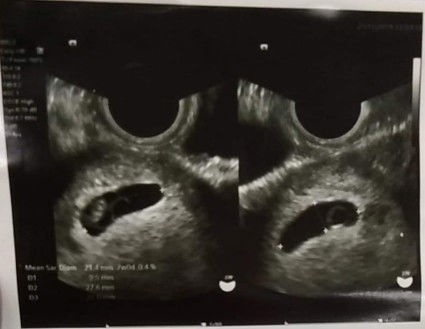

ตั้งครรภ์7w หัวใจไม่เต้น

รอบเดือนมาครั้งสุดท้าย 17 ก.ย.62 ไปหาคุณหมอวันที่ 21 พ.ย.62 คุณพยาบาล บอกว่าอายุครรภ์น่าจะ 9 สัปดาห์ พอคุณหมออัลตราซาวนด์ กลายเป็นเด็กอายุประมาณ 7 สัปดาห์ 9.9 m และไม่มีเสียงหัวใจเต้น หัวใจสลาย คุณหมอเลย บอกว่า คุณแม่อาจจะนับวันผิด เลยตอบคุณหมอว่า ไม่ผิดหรอกคะ จดไว้กับแอพทุกครั้ง คุณหมอเลยถามว่าประจำเดือนเลื่อนบ่อยมั้ยครับ เลื่อนบ่อยคะ คุณหมอเลยบอกว่า งั้นอาจเป็นได้ คุณหมอบอกว่า ไม่ค่อยปกติเท่าไรนะ คุณแม่อายุเยอะแล้วด้วย (39 แล้ว )เลยให้ตรวจเลือดเพื่อดูโฮโมน hcg ตรวจเลือดไปวันที่ 21 พ.ย. และ 23 พ.ย. คุณหมอแจ้งว่าวันพุธที่ 27 พ.ย. มาฟังผลพร้อมอัลตราซาวนด์ติดตามผลการตั้งครรภ์ ถ้าผิดปกติ หมอจะนัดขูดมดลูกนะ หัวใจสลายน้ำตาไหลข้างใน พอออกมาจาก รพ. น้ำตาไหลเป็นน้ำตก ไม่รู้จะทำยังไง กังวลไปหมด ถ้าเค้ามีชีวิตล่ะ เราจะฆ่าลูกมั้ย กังวลใจมากมาย ไปอ่านเจอการตั้งครรภ์ 10 สัปดาห์ หัวใจเด็กไม่เต้น แต่พอสัปดาห์ถัดไปเริ่มมีเสียงหัวใจ คราวนี้ยิ่งฟุ้งไปอีก อยากขอกำลังใจและคำแนะนำคะ ขอบคุณล่วงหน้าด้วยนะคะ